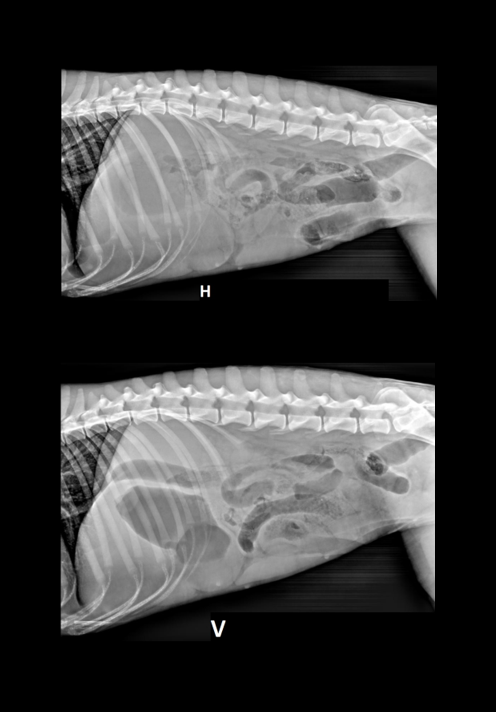

Denne gangen har vi lyst til å dele et kasus som vi syns er ganske interessant. Studien ble sendt inn til oss fra Dyrlegene i Skolestua, og sammen kom vi frem til en diagnose som kan forklare hundens problemer. Signalement: Pyreneerhund, tispe, 9år Anamnese: Eier syns hunden har blitt i dårligere form over tid, den bruker lang tid på å spise, tiltagende hosting. Eier har sau, så hunden jobber som vokterhund. Etter anstrengelse bruker hunden lang tid på restitusjon, peser lenge.